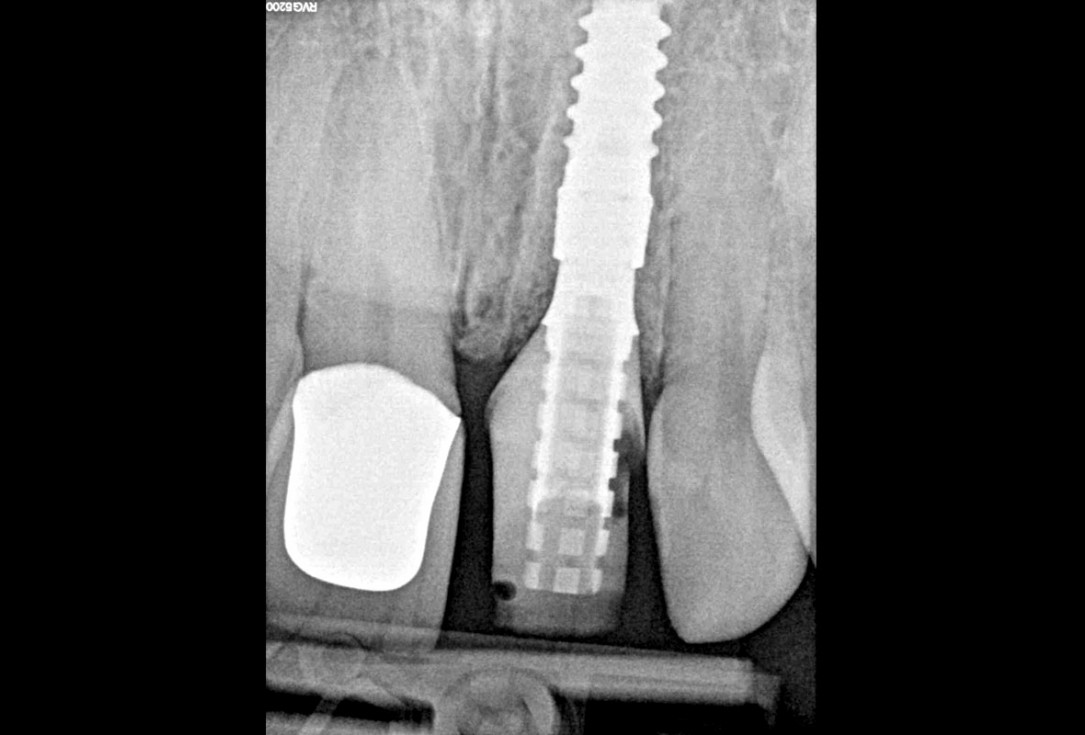

28/30 - Radiological control after surgeryExcellent aesthetic result of buccal augmentation with mucoderm® and maxgraft® after immediate implant placement - 3-years follow-up - Dr. A. Puišys

-